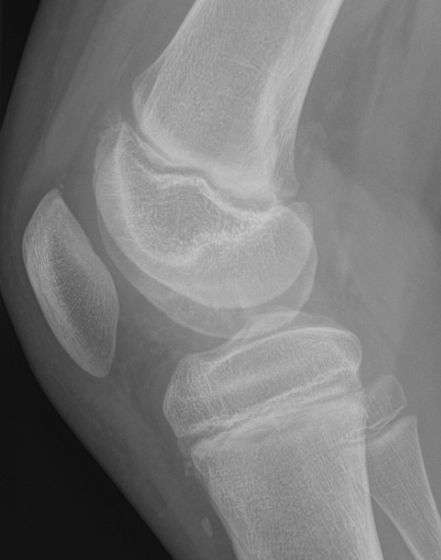

En broskbit med underliggande ben lossnar från metafys. Vanligast i mediala femurkondylen i ålder 10-19 år men kan hända i de flesta leder och även hos vuxna. [1, 2]

Osteokondrit i mediala femurkondylen hos 10-åring